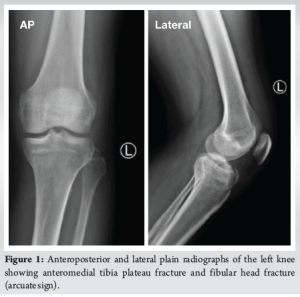

Imaging studies were done, including plain radiographs and computed tomography (CT), which revealed anteromedial rim fracture with anterior tibial eminence fracture of the left tibia and head of fibula fracture (arcuate sign) (Fig. 1 and 2). Although CT imaging provided adequate bony detail, no magnetic resonance imaging (MRI) was performed preoperatively to assess soft tissue structures. The presence of a fibular head fracture (arcuate sign), suggestive of possible PLC injury, was not explored further with advanced imaging due to financial considerations of the patient.

Case Report: A 44-year-old medically free male sustained a hyperextension injury to his left knee after being kicked by a horse. Imaging showed an anteromedial tibial plateau rim fracture, as well as a fibular head fracture. Examination under anesthesia revealed a stable knee. Open reduction and internal fixation were conducted using a 3.5 locking compression plate L-shaped plate, and screws. Post-operative outcomes at 7 months of follow-up, the patients had complete knee mobility, no significant ligamentous damage, and returned to regular activities without discomfort.